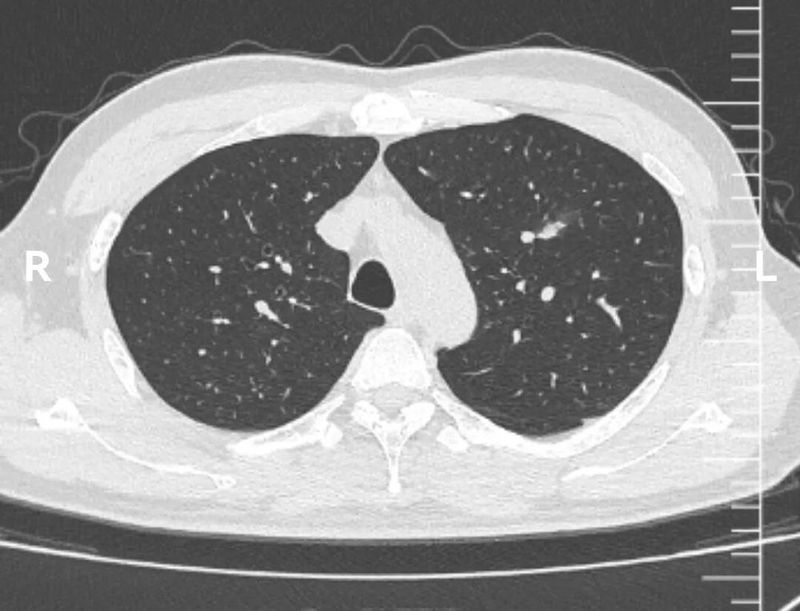

1个月后复查CT,该结节如愿明显吸收。